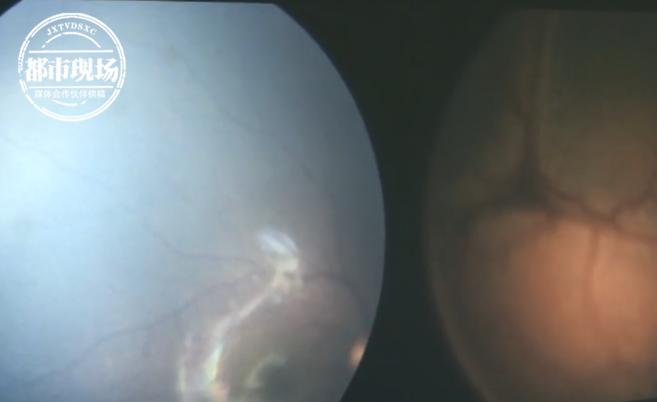

江蘇揚(yáng)州市民小李有個(gè)八月大的寶寶,最近她發(fā)現(xiàn)孩子眼睛異常:白天發(fā)亮,晚上還會(huì)像“貓咪”一樣反光。到醫(yī)院一查,事情不妙。 小李孩子眼睛的X光片,上面顯示,孩子的左眼里長(zhǎng)了一個(gè)巨大腫瘤。醫(yī)生介紹,小李的孩子只有八個(gè)月大,前不久發(fā)現(xiàn)異常后,來(lái)醫(yī)院進(jìn)行了檢查。 “家長(zhǎng)反映在家里發(fā)現(xiàn)孩子有只眼睛,有白色透亮的光,尤其是夜間非常的明顯,然后家長(zhǎng)得有點(diǎn)奇怪!

孩子最終被診斷患上了罕見(jiàn)的視網(wǎng)膜母細(xì)胞瘤。醫(yī)生介紹,這種腫瘤的發(fā)病率只有一萬(wàn)五到兩萬(wàn)分之一,并通過(guò)數(shù)字化成像系統(tǒng)繪制了腫瘤摸樣!霸谙旅媛∑鹁薮蟮哪[瘤,覆蓋了整個(gè)網(wǎng)膜。所以這個(gè)孩子情況是非常危重的,直接會(huì)危害孩子的生命健康安全!

考慮到腫瘤已經(jīng)發(fā)展至晚期,可能危及生命,醫(yī)生建議小李帶著孩子去上海進(jìn)一步治療。